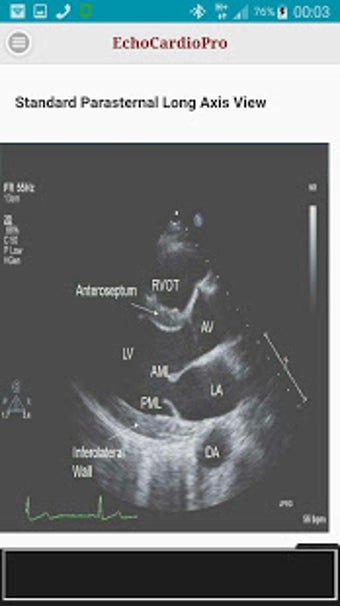

Aplikacja dostarcza kompleksowych informacji na temat echokardiografii przezklatkowej (TTE) i echokardiografii przełykowej (TEE) oraz ich odpowiednich korzyści w ocenie czynności skurczowej i rozkurczowej lewej i prawej komory, regionalnego ruchu ściany, wad zastawkowych serca i chorób osierdzia. Zawiera również szczegółowe informacje na temat różnych widoków, takich jak długoosiowy przysercowy, krótkoosiowy przysercowy, wierzchołkowy, podżebrowy, nadobojczykowy, śródprzełykowy, poprzezżołądkowy, głęboko poprzezżołądkowy i wysoko przełykowy.